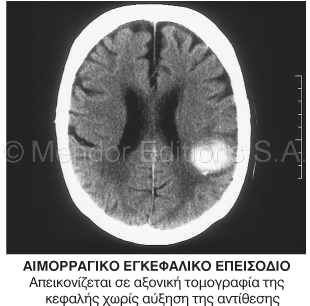

Βλ.: εικόνα.

1. Αιφνίδια απώλεια της νευρολογικής λειτουργίας, προκαλούμενη από αγγειακή βλάβη του εγκεφάλου. Τα εγκεφαλικά

επεισόδια είναι εξίσου συχνά και θανατηφόρα: περίπου 730.000 εγκεφαλικά επεισόδια συμβαίνουν στις Η.ΠΑ. ετησίως, ενώ η πάθηση αποτελεί την τρίτη

κυριότερη αιτία θανάτων στις Η.Π.Α. Εξαιτίας της μακροχρόνιας αναπηρίας που συχνά προκαλεί, το εγκεφαλικό επεισόδιο είναι η πιο επίφοβη πάθηση για τους

ηλικιωμένους Αμερικανούς. Στις Η.Π.Α., το 80% των εγκεφαλικών επεισοδίων προκαλείται από εγκεφαλική έμφραξη (έμφραξη των καρωτίδων ή των

ενδοεγκεφαλικών αρτηριών από θρόμβους ή αθηροσκλήρωση), ενώ η πλειονότητα των υπόλοιπων οφείλεται σε ενδοκρανιακή αιμορραγία ή εγκεφαλική

εμβολή. Οι πρόσφατες εξελίξεις στην αντιμετώπιση των εγκεφαλικών (π.χ. οι πρόοδοι στην πρόληψη, η πρώιμη χρήση θρομβολυτικών φαρμάκων, η αγγειακή

υπερηχογραφία και η ενδαρτηριεκτομή) έχουν φέρει επανάσταση στην οξεία και επακόλουθη μέριμνα των ασθενών.